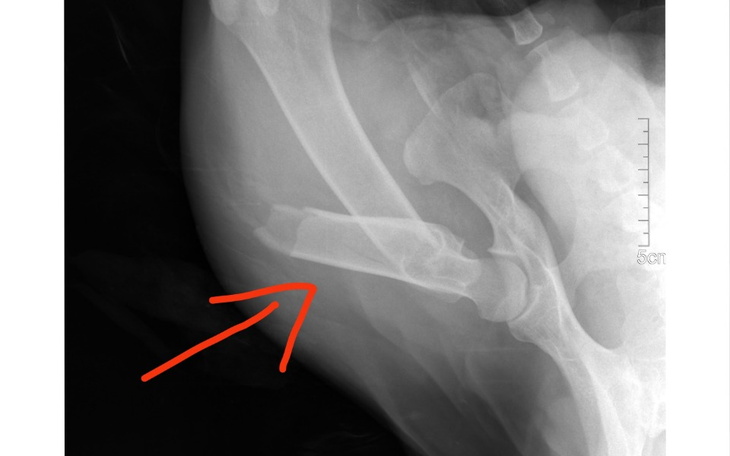

Baloo, bo tak dostał na imię, trafił do schroniska z okropnym złamaniem. Kość udowa w lewej tylnej łapie jest złamana w połowie długości.

Jedynym ratunkiem dla psiaka jest operacja, podczas której kość zostanie usztywniona na metalowej płycie.